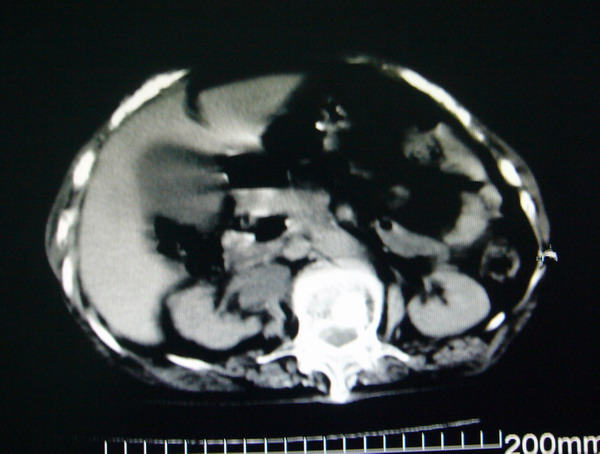

女:83y,转移性右下腹痛2小时,白细胞计数增高。

1.右侧肾盂扩大,肾盏无扩张,考虑:先天性肾盂变异可能性大。

2.胆囊扩张,考虑:胆囊炎。

3.阑尾区域可见以结节样高密度影,结合病史,考虑:阑尾结石,阑尾炎。

右下腹肠系膜增厚,结合病史支持阑尾炎.

右侧壶腹型肾盂可能,建议输路造影或增强

1.右侧肾盂扩大,考虑先天性肾盂变异或肾盂旁囊肿。

2.胆囊扩张,考虑胆囊炎。

3.阑尾区域可见结节样高密度影,结合病史考虑:阑尾结石、阑尾炎。